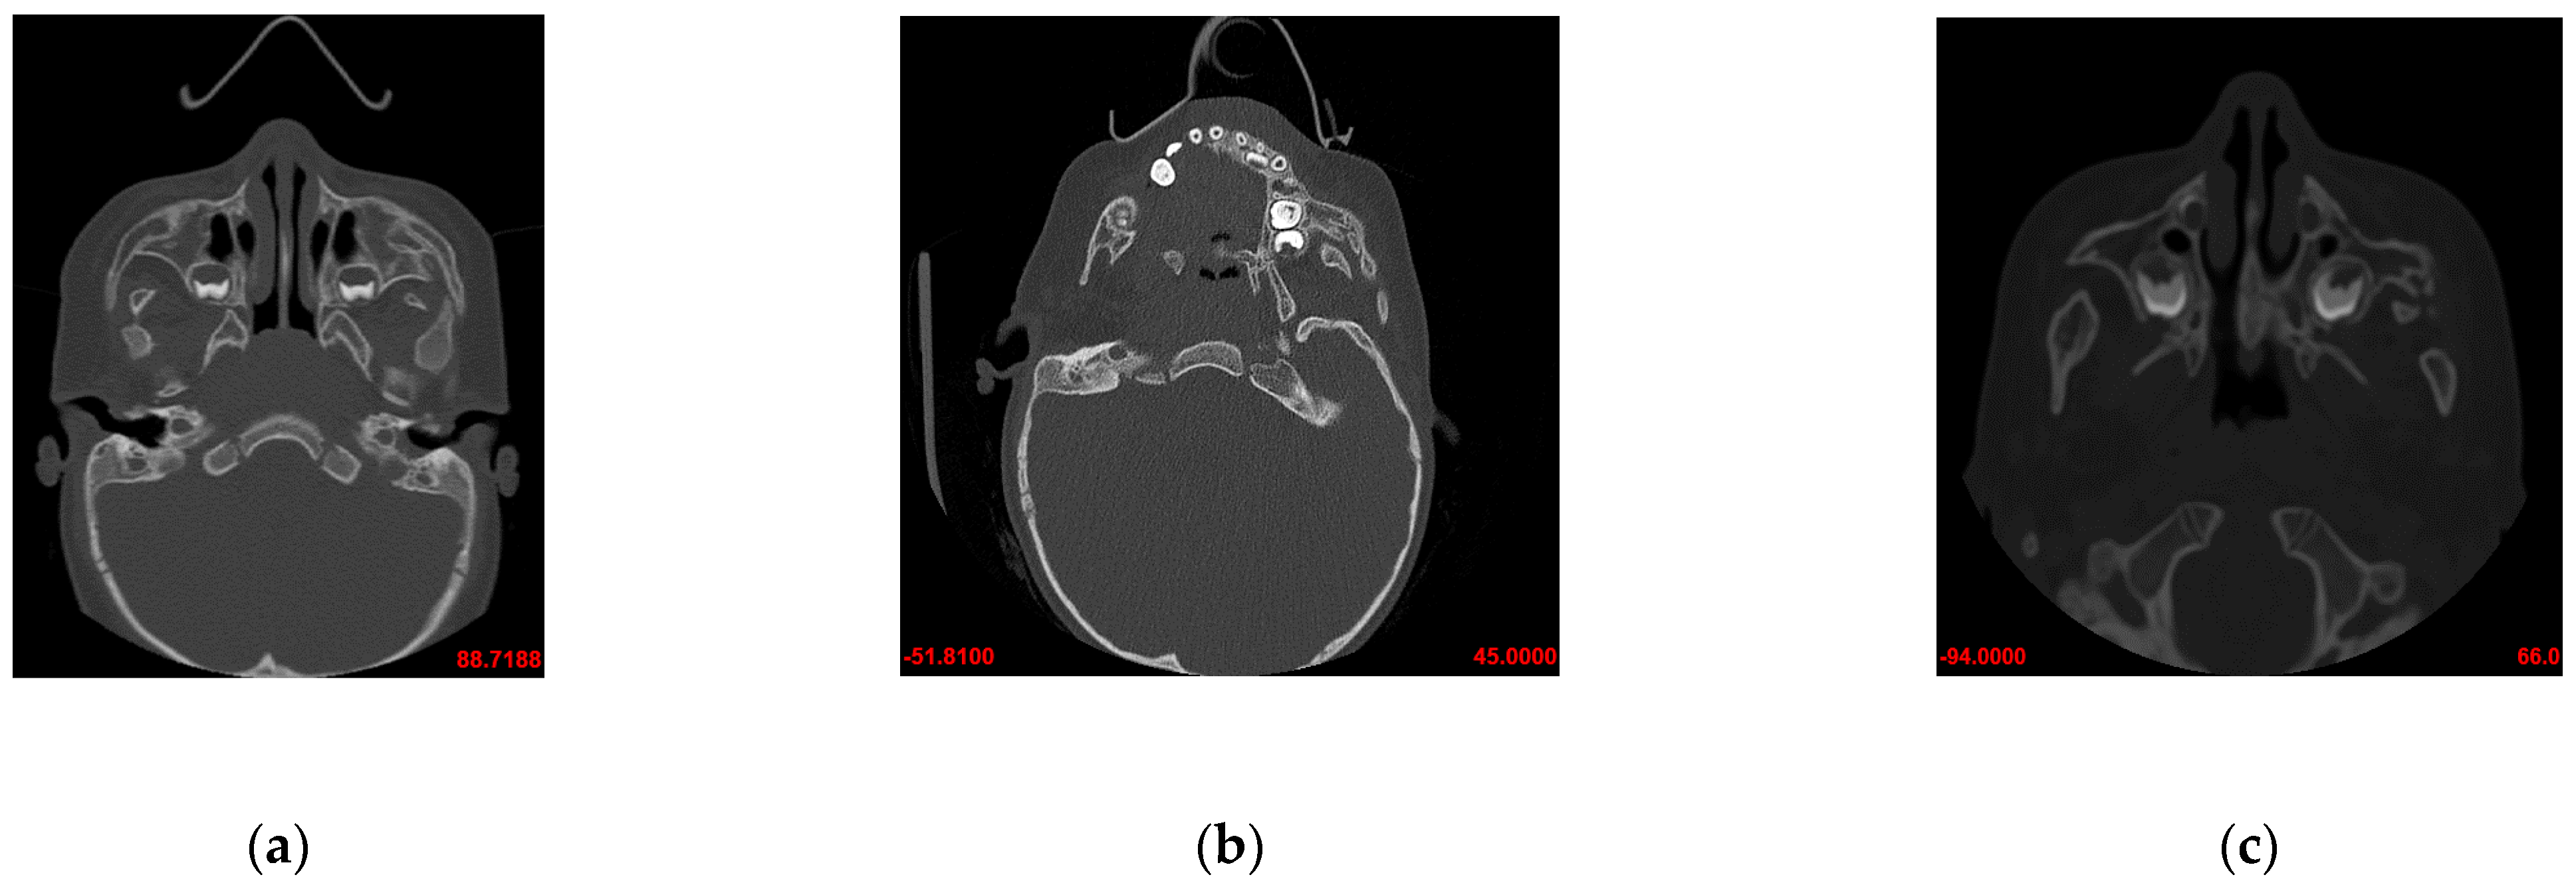

3.1. Prior to the Commencement of Treatment (Age—16 Months)

3.2. After the First Surgical Procedure and First Physiotherapy (Age—25 Months)

3.3. After Second Surgical Procedure and Second Physiotherapy (Age—54 Months)